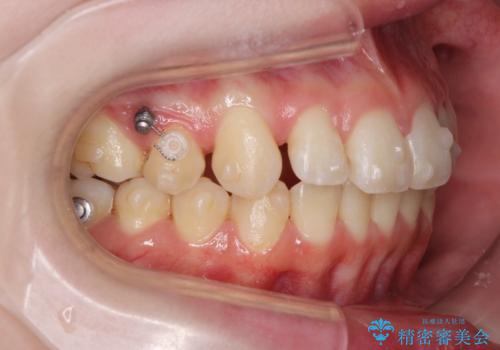

- 前歯の角度 奥歯の噛み合わせの改善をするために、矯正治療を希望され来院されました。

右側奥歯は上顎が相対的に前方に位置し(上顎前突)、そのため前歯の角度も突き出たようになり出っ歯のように見える状態でした。

マイクロインプラントを用いて、上顎奥歯を後方に移動させることで噛み合わせ・前歯の角度を改善していきます。

少し時間はかかりましたが、しっかりと綺麗な歯並びに仕上げることができ、大変喜んでいただくことができました。